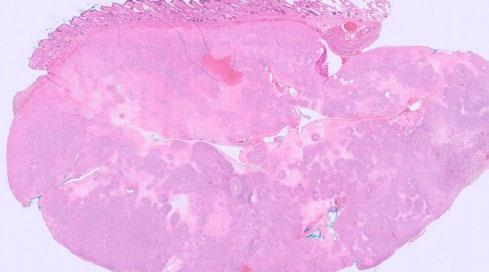

Figure 2. Low and high-power histopathology images of Isabella’s lump

given IM. The frequency in this case was weekly for weeks 1 – 4, then fortnightly for the next injection, and then monthly.